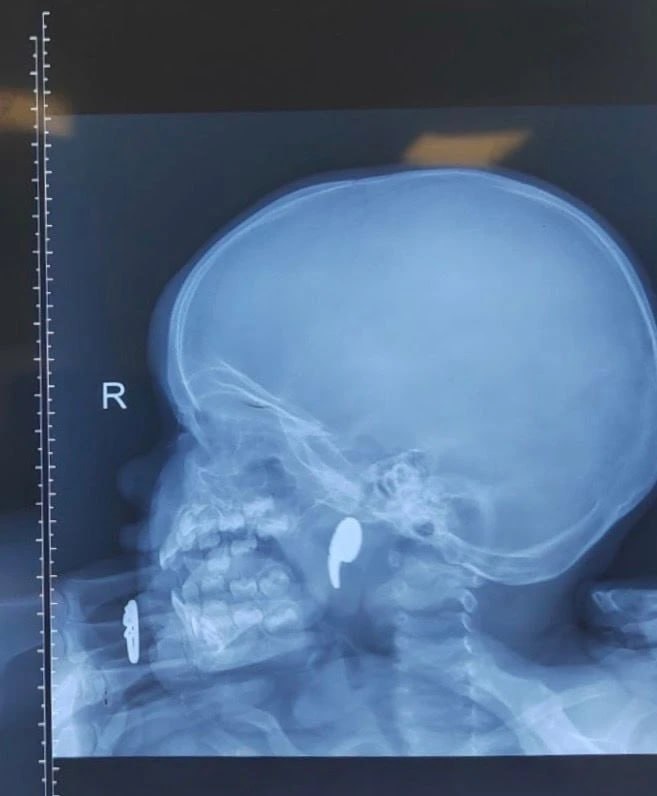

В областную больницу №1 обратились родители пострадавшей. Они рассказали, что девочка играла магнитом в форме запятой, а затем начала давиться. После попытки матери извлечь его пальцем, он сместился в носоглотку. У ребенка появились боль в горле, отказ от еды и слюнотечение.

После рентгенологического подтверждения наличия инородного тела, девочка была госпитализирована в оториноларингологическое отделение. Под общей анестезией и эндоскопическим контролем был успешно извлечен магнит. На следующие сутки ребенок был выписан домой под наблюдение педиатра.